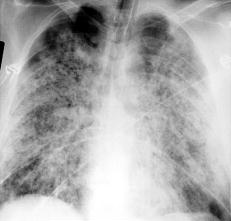

氣胸

有些人,特別是老年慢阻肺患者,在用力咳嗽、劇烈運(yùn)動(dòng)或大笑后,會(huì)發(fā)生氣胸,出現(xiàn)胸痛、深吸氣時(shí)加劇,并放射到肩背部,嚴(yán)重時(shí),還會(huì)出現(xiàn)呼吸困難、血壓下降等緊急情況。遇到這種情況,禁忌拍背和搬動(dòng)患者,以免加重氣胸。應(yīng)讓患者取半臥位,如家中備有氧氣,應(yīng)立即吸氧,同時(shí)叫救護(hù)車。